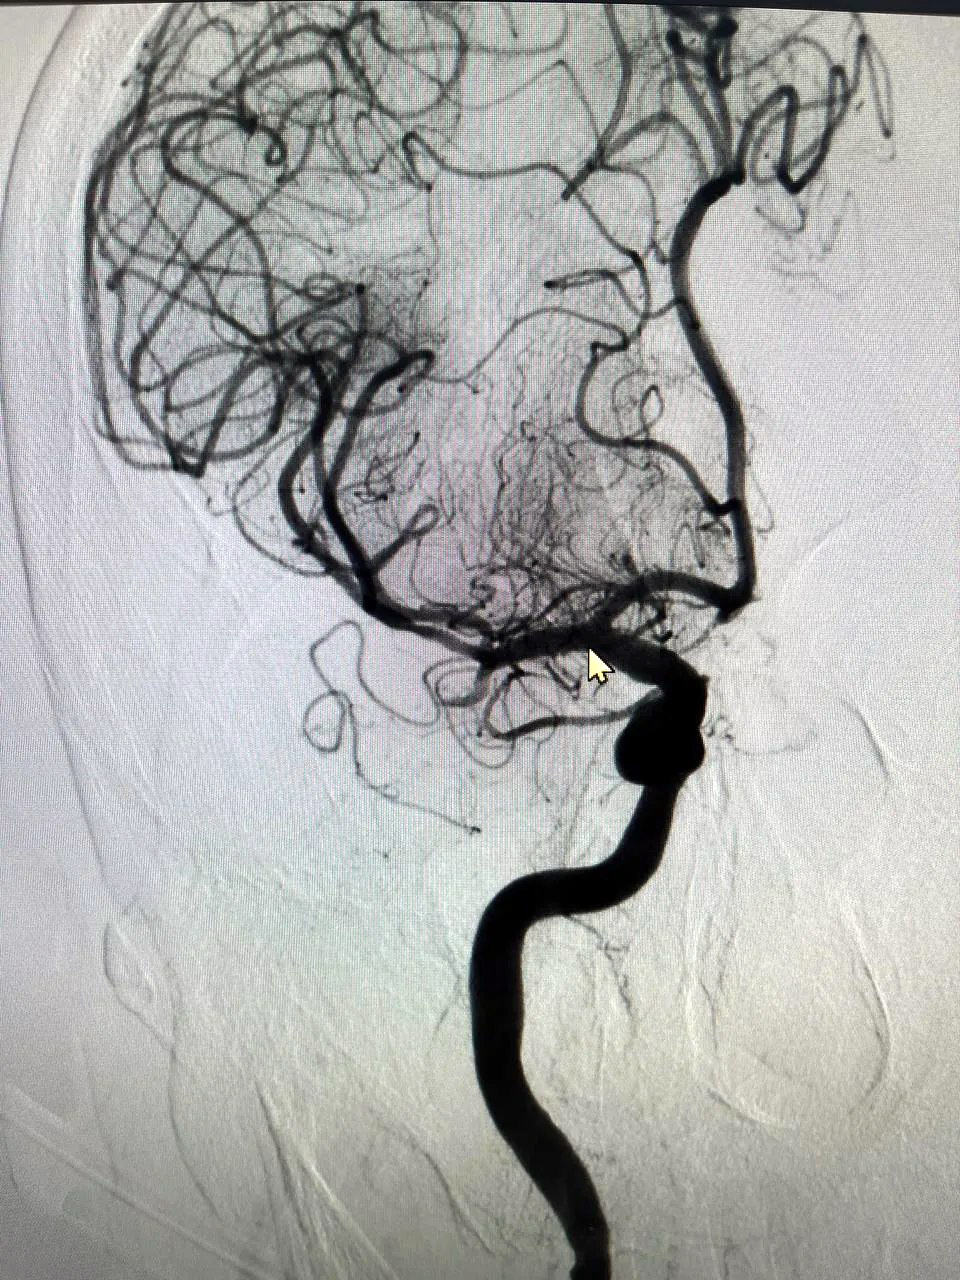

Как сообщает телеграм-канал БГКБ, процедура, называемая эндоваскулярной тромбэкстракцией, является мировым стандартом лечения ишемического инсульта. Её суть – в механическом извлечении сгустка крови, блокирующего артерию, через минимальный прокол. Это позволяет мгновенно восстановить кровоток и в разы увеличить шансы пациента на полное восстановление без тяжелой инвалидности.

В настоящее время прооперированный пациент находится под наблюдением в отделении реанимации, где получает необходимое лечение. На снимках, предоставленных больницей, запечатлены тромбы, ставшие причиной инсульта и успешно извлеченные из мозговых артерий.